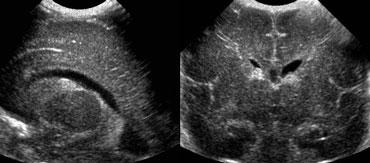

Xuất huyết nội sọ độ 2

Hình bên trái là xuất huyết nội sọ độ 2.

Trên mặt cắt đứng ngang, chỉ nhìn thấy khoang vách trong suốt.

Cả hai não thất bên đều chứa đầy máu, nhưng không có giãn não thất.

Hình bên trái là cùng bệnh nhân sau 3 ngày.

Các não thất giãn rộng và có hình ảnh hình thành cục máu đông.

Não úng thủy thứ phát xảy ra vài ngày sau xuất huyết độ 2 không nên bị nhầm lẫn với xuất huyết độ 3.